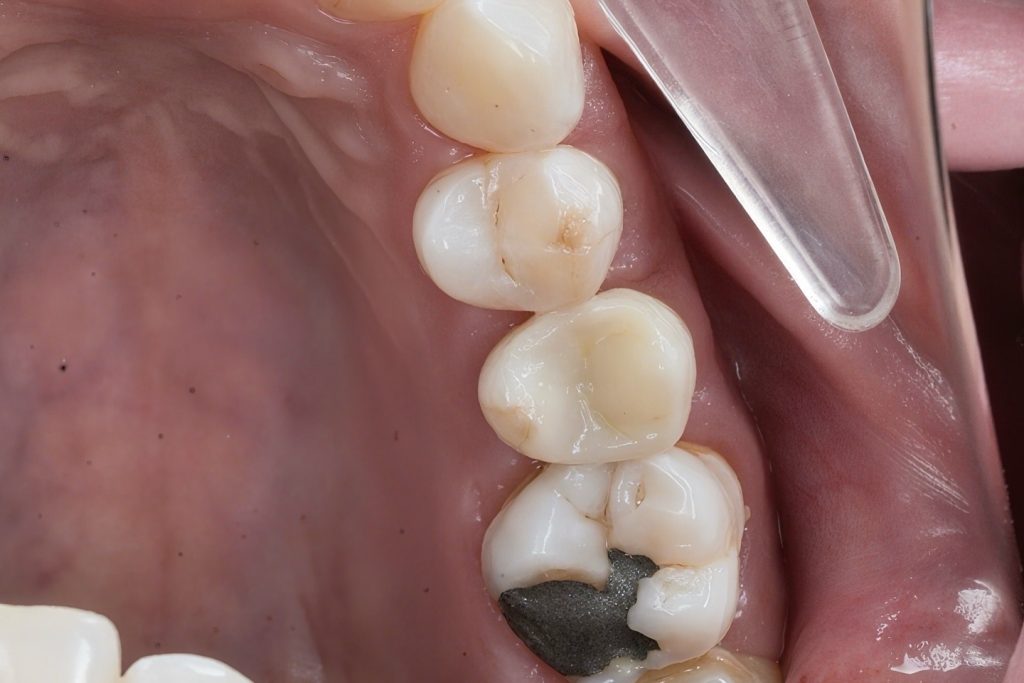

Patient reported food impaction and sensitivity during mastication between upper posterior teeth.

Clinical and radiographic exam confirmed adjacent Class II carious lesions affecting both teeth, with secondary caries beneath existing composite and defective margins.

Rubber dam isolation achieved using clamp stabilization to maintain a dry and clean operative field – essential for adhesive dentistry (Fig 1–2).

- Preoperative occlusal view showing defective composite & caries

- Rubber dam isolation